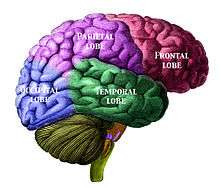

Left frontal lobe (click to view animation) Lobes

Base of brain. Human brain showing the four major lobes of the cerebrum. Beneath the cerebral cortex are the cerebellum, pons, olive, and medulla oblongata

Human brain showing the four major lobes of the cerebrum. Beneath the cerebral cortex are the cerebellum, pons, olive, and medulla oblongata Drawing to illustrate the relations of the brain to the skull.